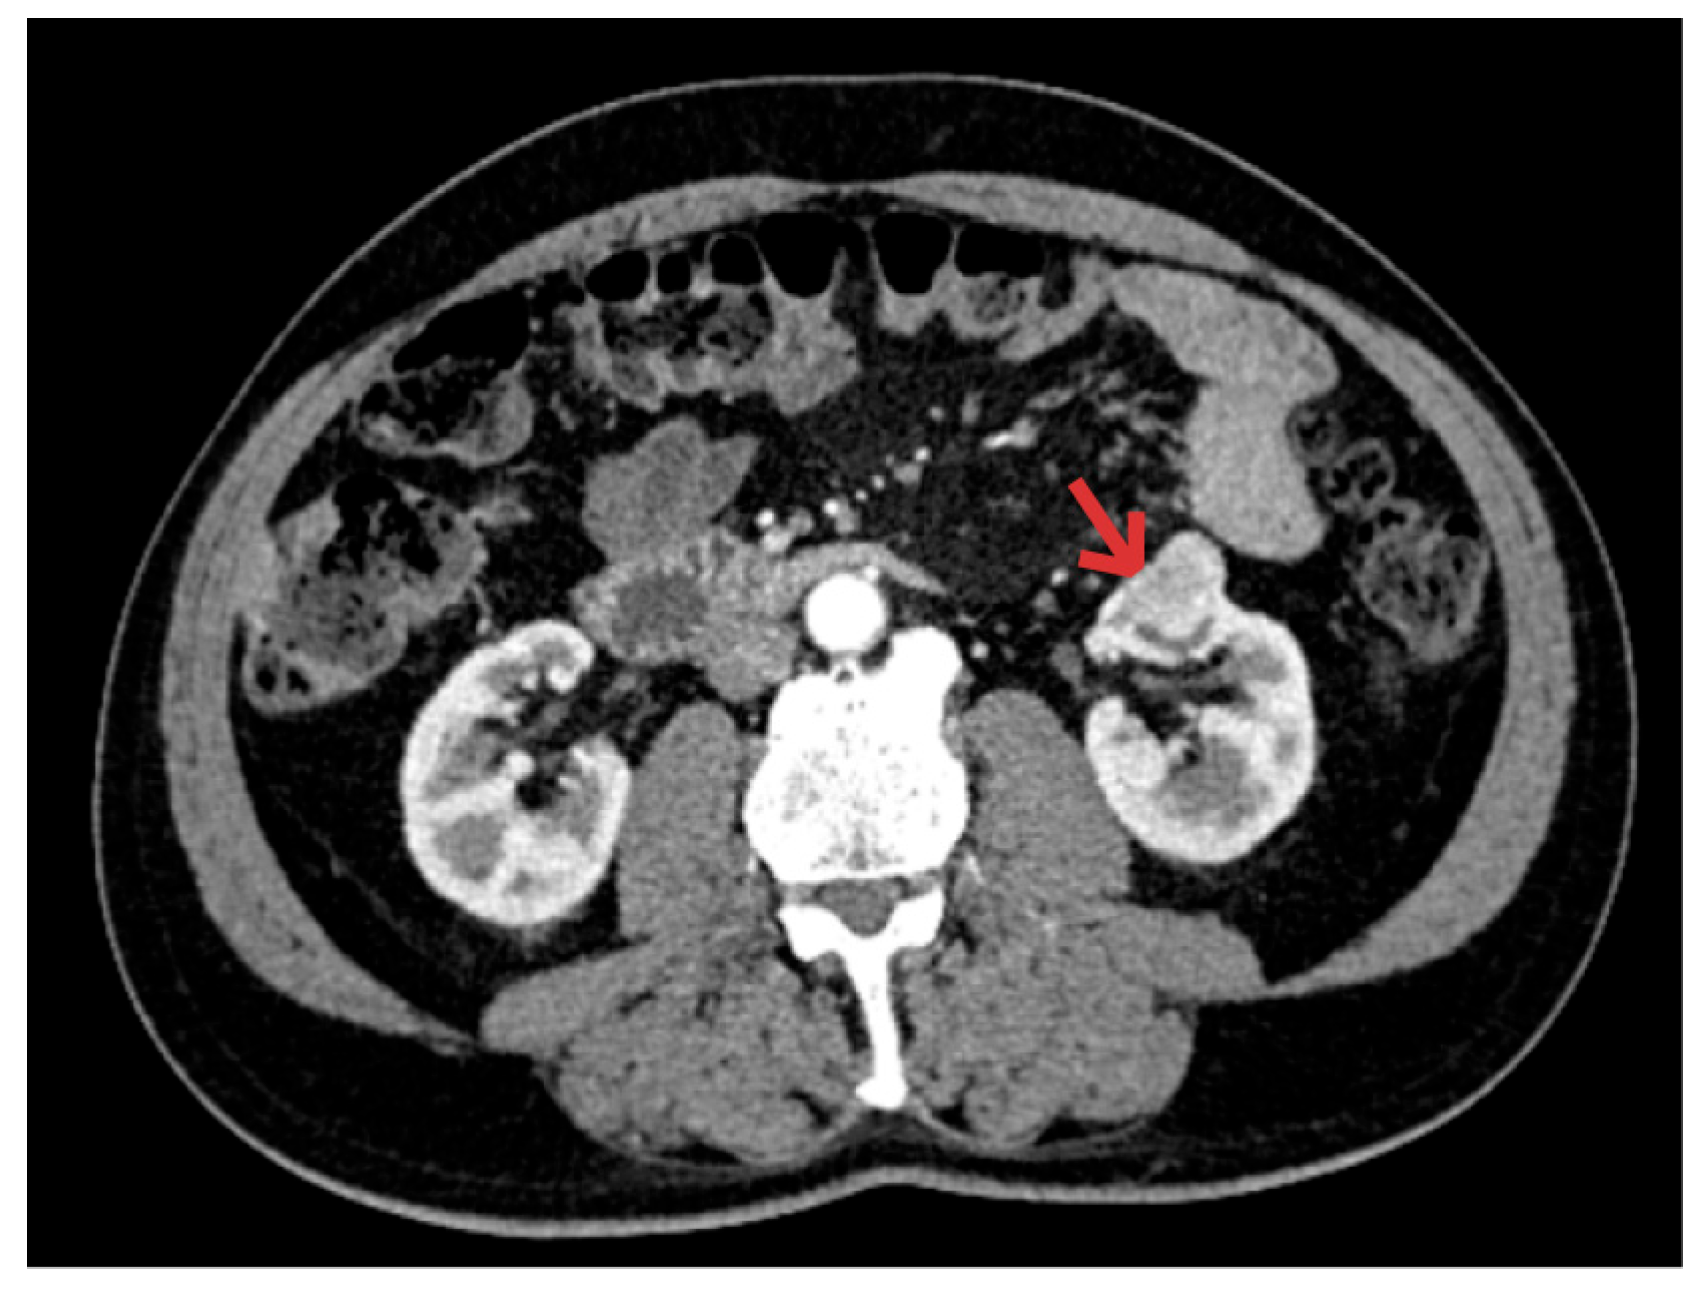

- The second synchronous tumor is usually a renal tumor, found during additional preoperative tests for colon tumor staging. This underscores the value of imaging not only for metastatic assessment but also for identifying additional primary malignancies. Our study confirms this frequent finding in the literature.